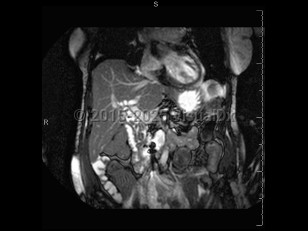

Acute cholangitis is acute inflammation and subsequent infection of the common bile duct. Acute cholangitis typically occurs in the setting of obstruction of the common bile duct. Common etiologies of obstruction include gallstones, strictures (from pancreatitis, biliary procedures, or autoimmune conditions), and malignancy. External compression from the duodenum may also result in obstruction and stasis.

More recently, the Tokyo Guidelines include laboratory tests and imaging to further define the diagnosis of cholangitis (MDCalc: Tokyo Guidelines).